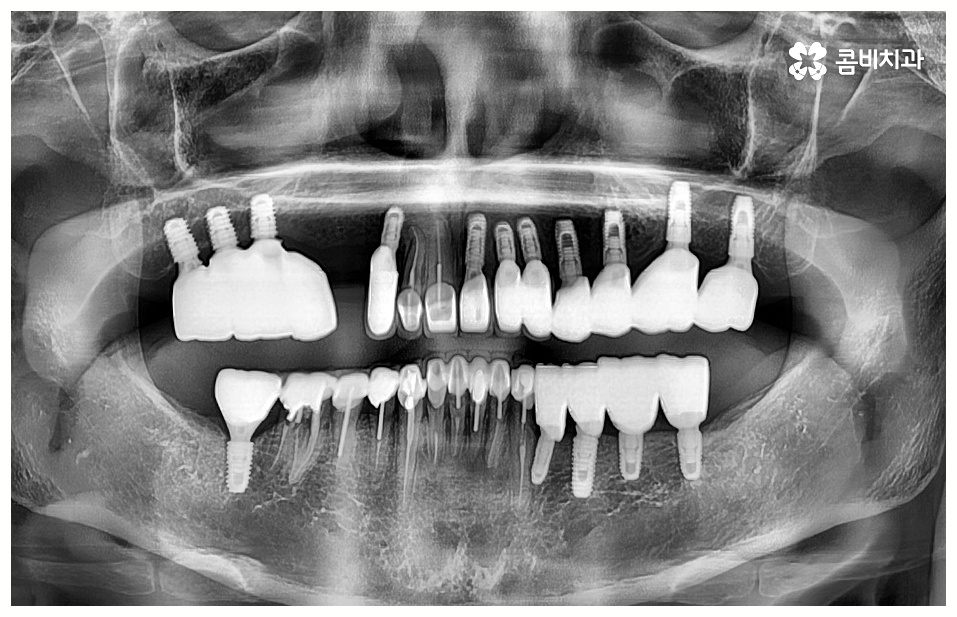

임플란트 시술을 받을 때 많은 분들이 궁금해 하시는 것 중 하나가 임플란트 치료기간 그리고 수명에 대한 것일 텐데요, 먼저 기간은 대략적으로 3~6개월 정도 걸린다고 알려져 있으나 환자마다 잇몸뼈 상황이나 전체적인 건강 상태 및 회복력이 다르기 때문에 환자분들에 따라 다르게 적용되고 있는 부분이고 그에 따라 임플란트 치료기간 또한 달라질 수 있습니다.

임플란트 치료는 자신의 자연 치아를 대신해 오랫동안 쓸 수 있도록 장기적인 안정성을 추구하는 것이 중요하기 때문에 최초의 진단과 치료 계획을 꼼꼼하게 세우는 것이 필수라고 할 수 있어요.

또한 풍부한 임상 경험과 노하우를 가진 숙련된 의료진, 다각적이고 체계적인 분석을 할 수 있는 3D CT 와 같은 정밀 분석 장비를 갖추고 보다 안정성이 검증된 정품 재료의 사용 여부 등을 잘 체크해야 할 거예요.

임플란트 수명은 개인차가 있겠지만 잇몸 케어 등 사후 관리 역시 철저하게 해 주신다면 반영구적인 사용도 가능한 만큼 치과에서 알려드리는 주의 사항을 잘 따라주시고 검진 및 스케일링 등에 신경 쓰시고 꾸준히 믿고 찾을 치과를 잘 선택해야 할 수 있어요.